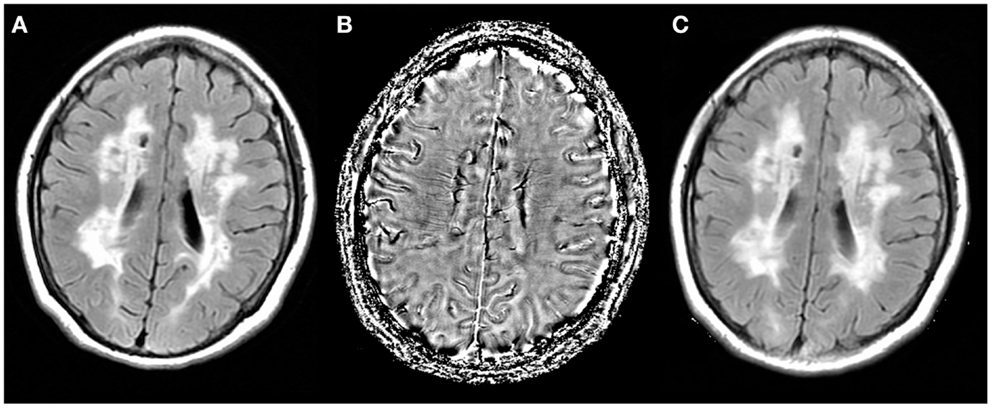

Fazekas grades. Мультифокальная лейкоэнцефалопатия. Резидуальная энцефалопатия на мрт. Прогрессирующая мультифокальная лейкоэнцефалопатия кт. Гипертензионная энцефалопатия на мрт.

Fazekas grades. Мультифокальная лейкоэнцефалопатия. Резидуальная энцефалопатия на мрт. Прогрессирующая мультифокальная лейкоэнцефалопатия кт. Гипертензионная энцефалопатия на мрт.